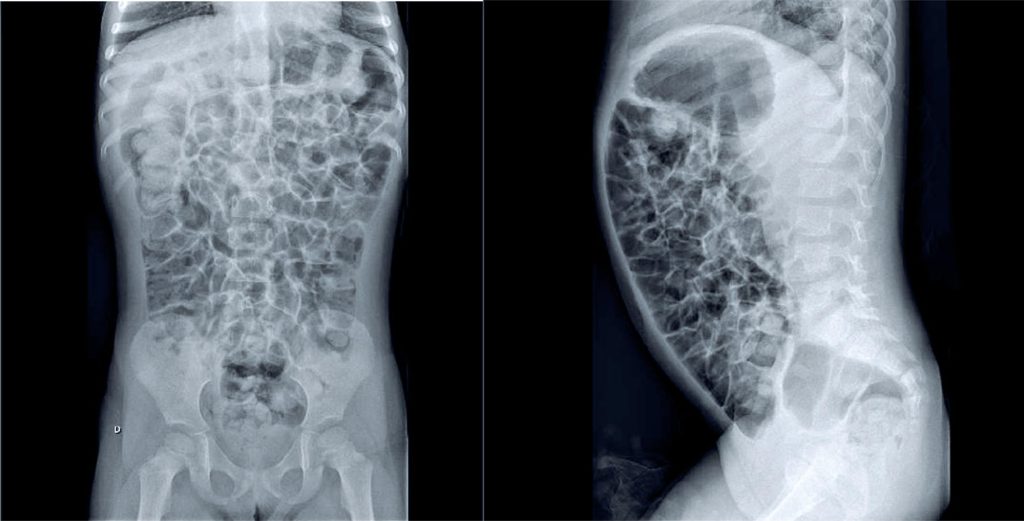

A 3.5-year-old female presented with a 10-month history of abdominal pain and distension, accompanied by frequent belching and flatulence. No nausea, vomiting, or nighttime awakening due to pain was reported, and the patient’s appetite remained intact. Growth and development were age-appropriate (weight: 16.2kg, height: 106cm). She was born at term without complications and had a normal neonatal screening. No comorbidities typically associated with small intestinal bacterial overgrowth (SIBO)—such as prior intensive care unit admission, immunodeficiency, food intolerance, Helicobacter pylori infection, anatomical abnormalities, prior abdominal surgeries, motility disorders, autoimmune conditions, or hepatic condition—were identified. Initial diagnostic hypotheses included more prevalent gastrointestinal disorders such as lactose intolerance, celiac disease, intestinal parasitosis, chronic constipation, and intestinal malformations (e.g., intestinal malrotation). SIBO was suspected following a thorough reassessment of the clinical history. The diagnosis was confirmed via a hydrogen breath test with lactulose, supported by radiological findings. Following treatment with metronidazole (30 mg/kg/day for 10 days), the patient demonstrated significant clinical resolution of the previously reported symptoms. A follow-up hydrogen breath test revealed no further evidence of bacterial overgrowth in the small intestine.